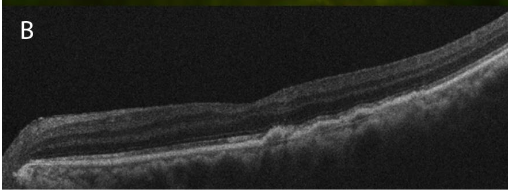

A 64-year-old female with diabetes and hypertension presented to the clinic complaining of two weeks of left eye pain, redness, and worsening vision. The patient’s ocular history was notable for idiopathic polypoidal choroidal vasculopathy (IPCV) complicated by macular hemorrhage in the left eye, successfully treated with pneumatic displacement and intravitreal injection of anti-vascular endothelial growth factor (anti-VEGF) and tissue plasminogen activator (tPA). She presented for a routine appointment for continued intravitreal anti-VEGF injections. BCVA in the affected eye following the macular hemorrhage was 20/70. At the time of her routine injection appointment, she had reported two weeks of worsening left eye pain, redness, and decreased vision. The BCVA of the left eye was 20/80, and she had severe anterior chamber inflammation with 270 degrees of posterior synechiae. Posteriorly, exam was notable for vitreous inflammation, exudative retinal detachment, and new gray-white choroidal lesions in the posterior pole.

The patient was started on oral and topical steroids with a resultant improvement of the exudative detachment, and her BCVA improved to 20/60. Despite this, the previously noted gray-white choroidal lesions increased. Fluorescein angiography was relatively unremarkable, without vasculitis or optic disc inflammation. A laboratory evaluation revealed positive IGRA, confirming tuberculosis infection. The patient urgently returned for a sudden change in vision and new photopsias, after two weeks of significant improvement on oral and topical steroids and cycloplegia. Her BCVA worsened to 20/100, and the exam showed increased number of choroidal lesions, new small retinal holes, and a new rhegmatogenous retinal detachment.

Infectious Disease specialists evaluated the patient. This patient too was from the Philippines, which was the only identified risk factor. No pulmonary or other extrapulmonary involvement was present. RIPE therapy was initiated before ophthalmic surgical intervention. Subsequently, the patient underwent repair of the complex retinal detachment with combined cataract extraction and retinal detachment repair with a silicone oil tamponade. Following surgery and RIPE therapy, the patient’s visual acuity remained stable at 20/200, and her retina remained flat with a resolution of the choroidal lesions.